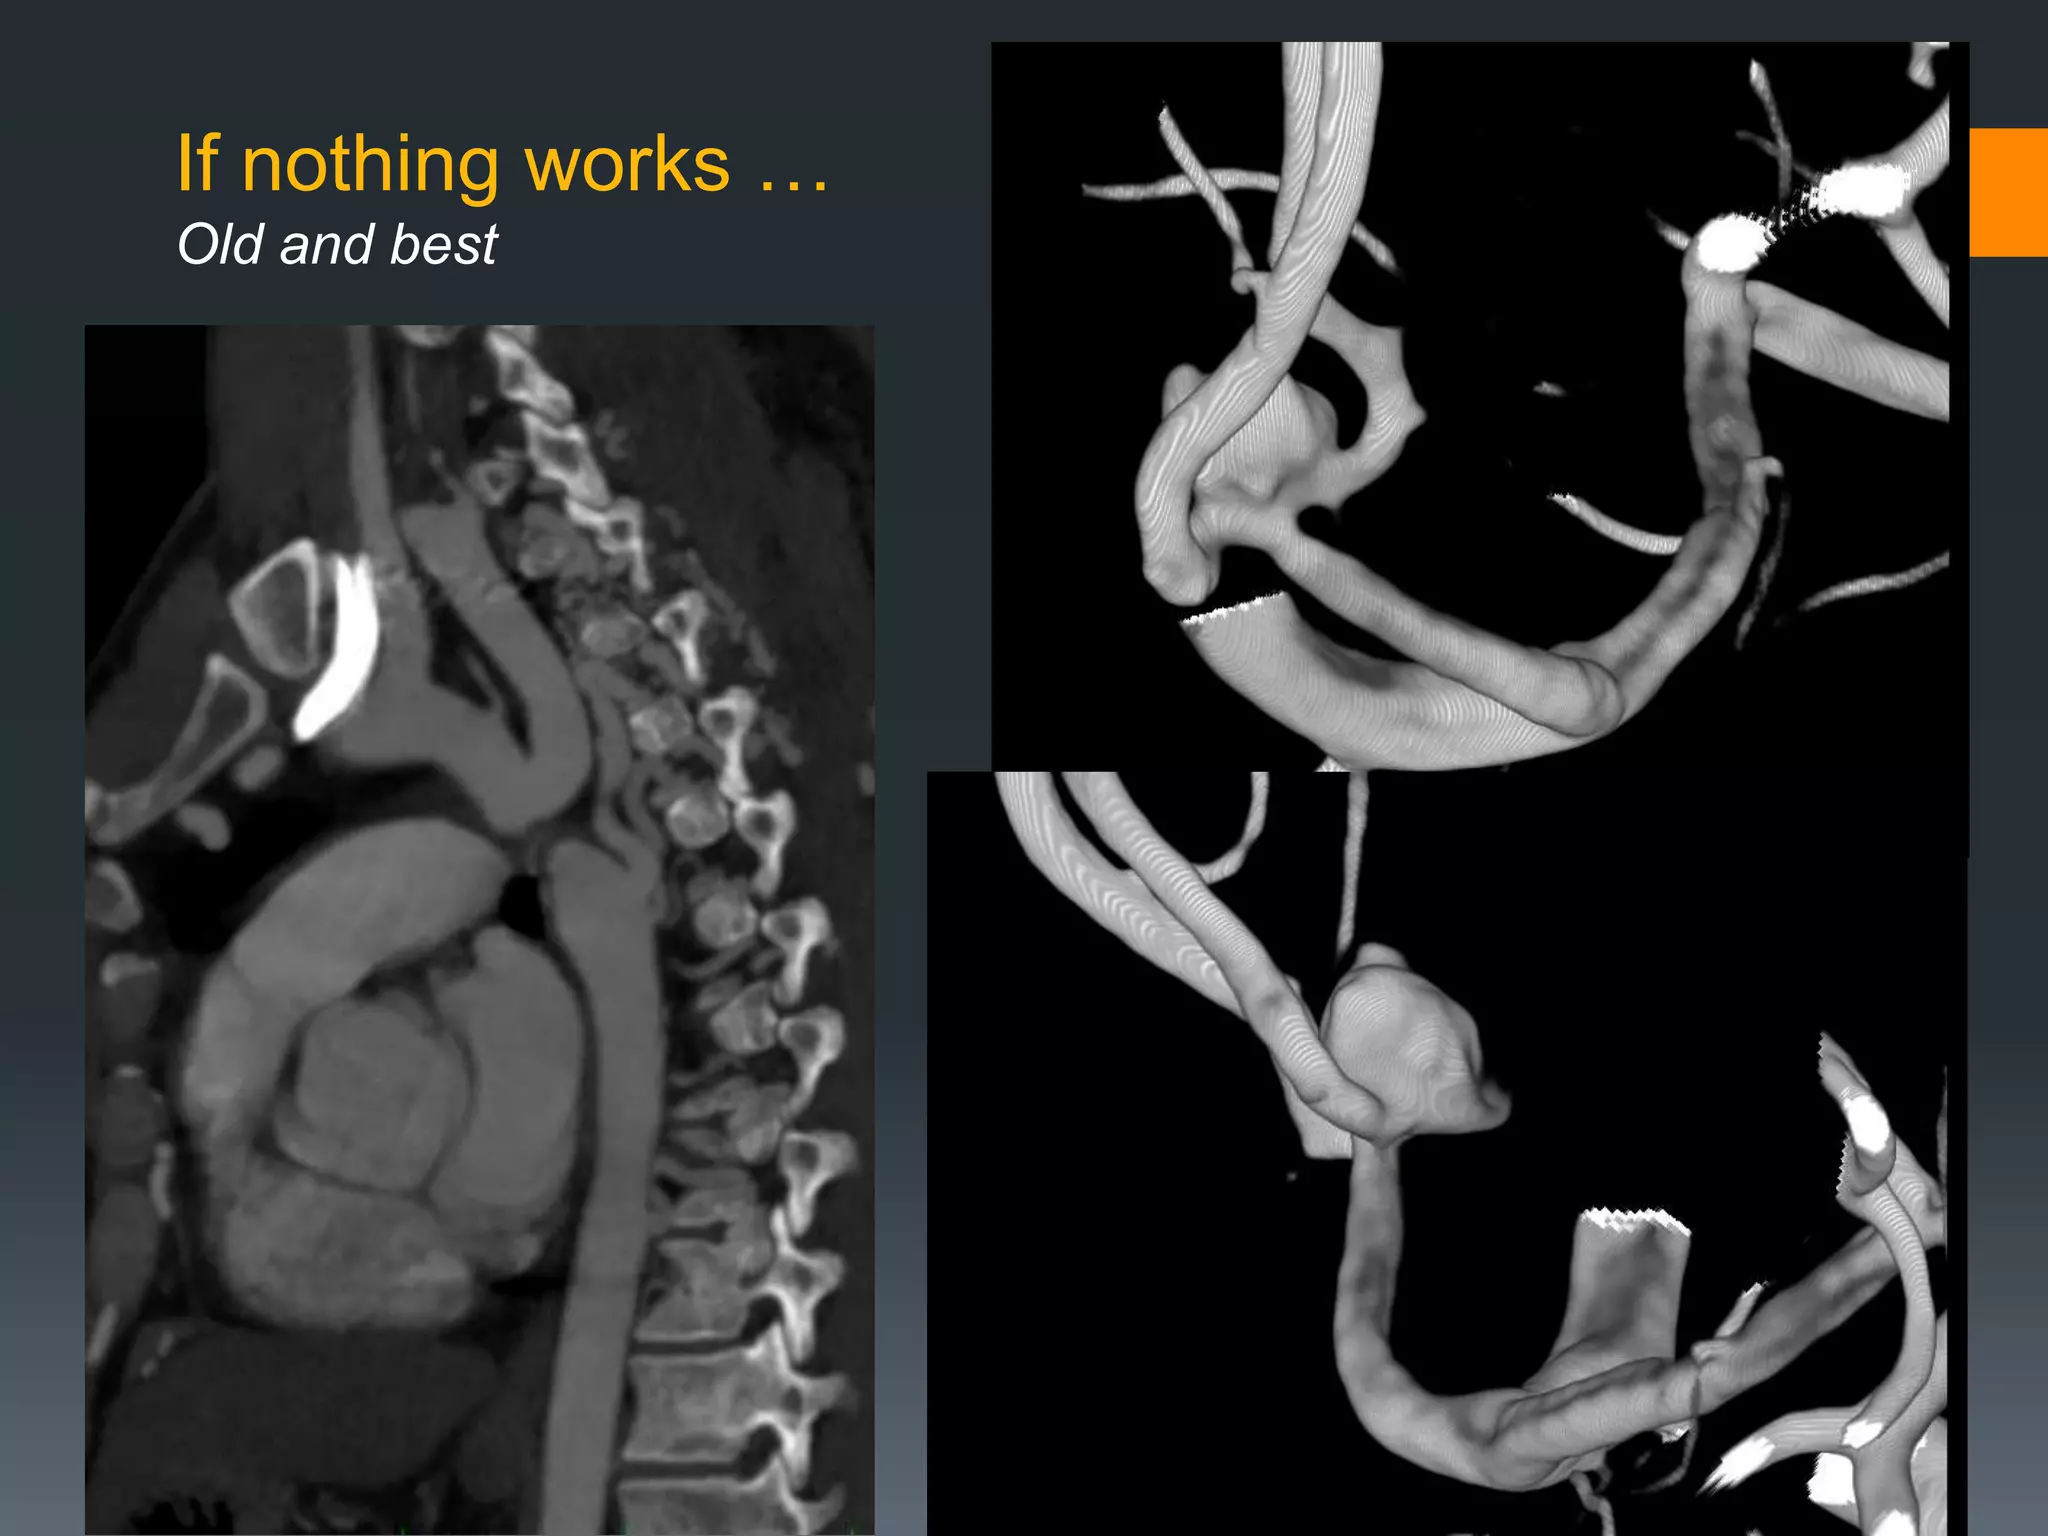

This document discusses tricks and techniques for difficult cannulations during neurointerventional procedures. It outlines strategies for accessing the aortic arch, internal carotid artery (ICA), and areas distal to aneurysms. Long sheaths, distal access catheters, and co-axial techniques are presented as options that have improved cannulation success. Guidance on sheath and catheter selection is provided for different vessel paths. The importance of catheter placement as high as possible in the ICA is emphasized. Reverse curve cannulations are also mentioned. Overall, the document stresses that careful cannulation is critical for procedural success and different strategies may be needed depending on the vessel target.